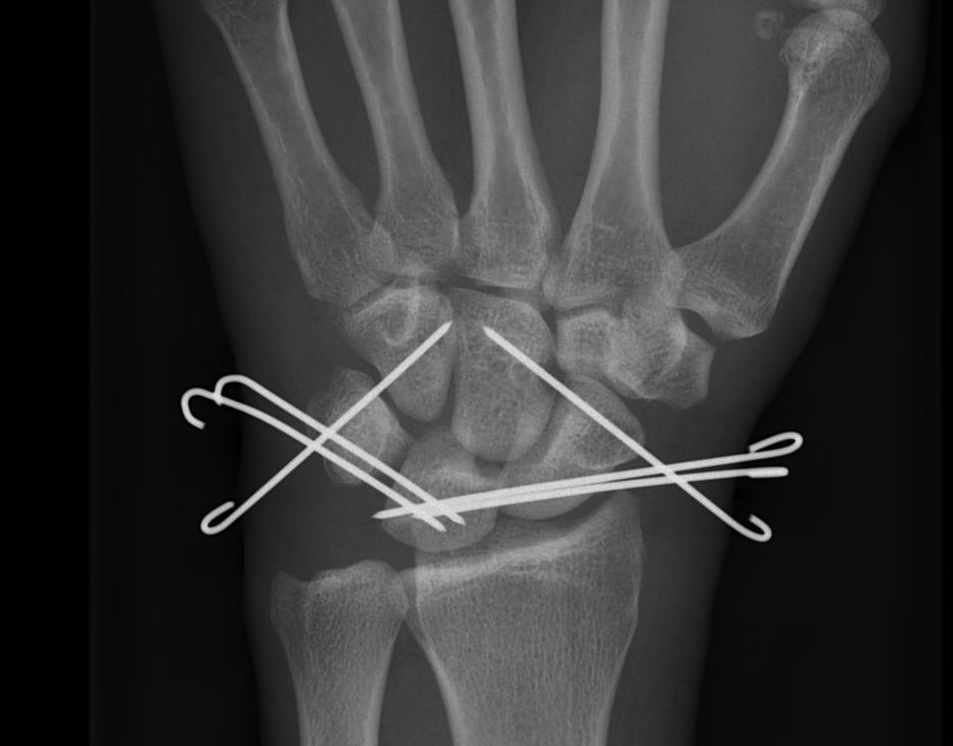

X-ray

Disruption of Gilula's 3 smooth carpal arcs

2. Trans Scaphoid Perilunate

Dorsal approach

- ORIF scaphoid fracture

- repair LT ligament

- K wires LT and TC (SL ligament is intact)

- ORIF capitate